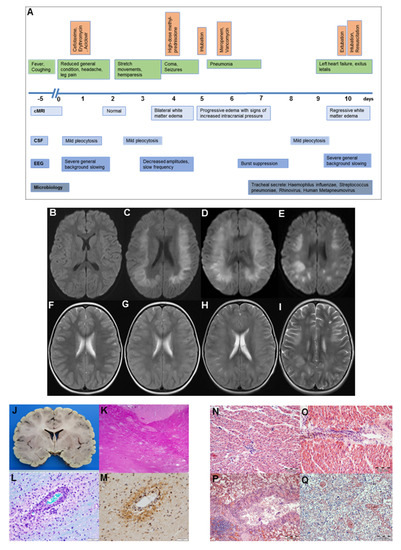

2. Case Report